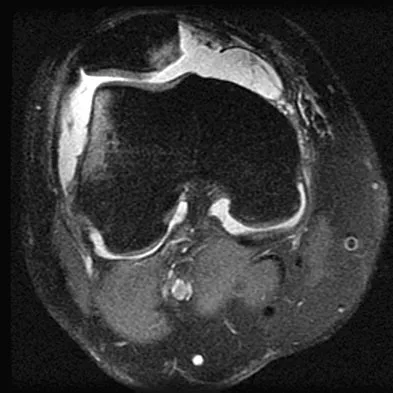

A 78-year-old woman undergoes her third lumbar decompression and fusion from L3 to L5 without complication. On the morning of postoperative day 3, examination reveals painless, flaccid weakness of both lower extremities. She also has an absent bulbocavernous reflex and a mild saddle paresthesia. MRI scans of the lumbar spine are shown in Figures 26a and 26b. What is the most appropriate management at this time?